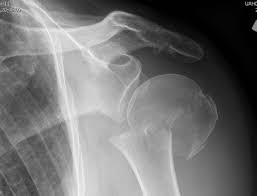

Question 12

A 55-year-old patient presents with a slowly enlarging, painful mass in the proximal humerus.

Biopsy reveals a hyaline cartilage matrix with cellular atypia, confirming a diagnosis of central conventional chondrosarcoma. Which of the following genetic mutations is most frequently identified in this specific tumor?

Explanation

Mutations in the isocitrate dehydrogenase genes, IDH1 and IDH2, are found in up to 50-60% of central conventional chondrosarcomas and enchondromas. EXT1 and EXT2 mutations are characteristic of multiple hereditary exostoses (osteochondromas). GNAS mutations are seen in fibrous dysplasia. TP53 and RB1 mutations are hallmark aberrations in osteosarcoma.